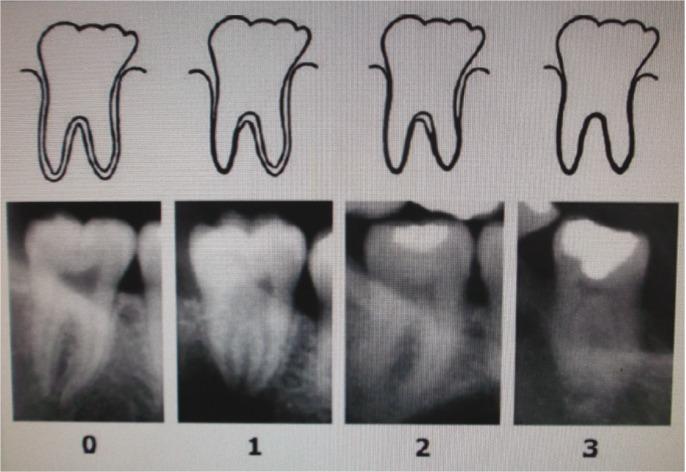

STUDY DESIGN

Periodontal ligament visibility was assessed in the lower third molars, using a sample of 487 orthopantomograms, 228 of which belonging to females and 259 to males, from a Portuguese population aged 17 to 31 years. A classification of four stages based on the visual phenomenon of disappearance of the periodontal ligament of fully mineralized third molars was used. For each stage, median, variance, minimal and maximal age were assessed.

采用487张全景X线片样本评估下颌第三磨牙的牙周膜可见性,这些样本来自17至31岁的葡萄牙人群,其中228份属于女性,259份属于男性。根据完全矿化第三磨牙牙周膜消失的视觉现象进行了四个阶段的分类。对每个阶段评估中位数、方差、最小和最大年龄。